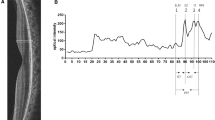

SD-OCT scans were acquired using the Spectral–domain Heidelberg retinal angiograph + optical coherence tomography (SD-HRA + OCT)© Heidelberg Engineering. The OCT component of the machine is a spectral/Fourier domain OCT with 5 μm axial resolution and an image acquisition speed of 40,000 scans/second. It employs a broad band 870 nm super luminescent diode source. Sixteen OCT scans were averaged to reduce noise. An experienced operator certified by the DARC (Digital Angiogram Reading Center, USA) acquired all images through a dilated pupil. Two independent observers (PBC and AKK) did the measurements in horizontal and vertical scans through the fovea by first magnifying the OCT scan 400% (Fig. 1a) and the values were averaged.

The central retinal thickness (CRT): distance between the internal limiting membrane (ILM) and the outer border of the retinal pigment epithelium (RPE) at the fovea.

The photoreceptor outer segment length (PROS) - distance between the inner border of the EZ and the inner border of RPE. [12]

The foveal outer segment pigment epithelial thickness (FOSPET) - distance between the EZ and the outer border of the RPE, measured at the thinnest point of fovea (Fig. 1b). [13]

Magnification of the central OCT (dashed box in (a)) by 400% for measurement of the outer retinal features. ELM - external limiting membrane, EZ or IS/OS - ellipsoid zone, RPE retinal pigment epithelium, CRT - central retinal thickness, PROS - photoreceptor outer segment, FOSPET - foveal outer segment pigment epithelial thickness (b)

Extent of the preserved EZ line was also measured in horizontal and vertical scans, centered at the fovea (Fig. 2). All measurements were done using the calipers of the Heidelberg reader software [14].